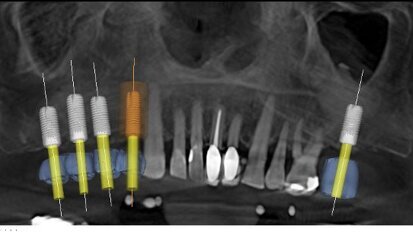

Planification prothétique rapide et facile

La plainte principale et la plus importante de cette jeune femme de 17 ans était le manque d'esthétique. Elle s'est également plainte ...